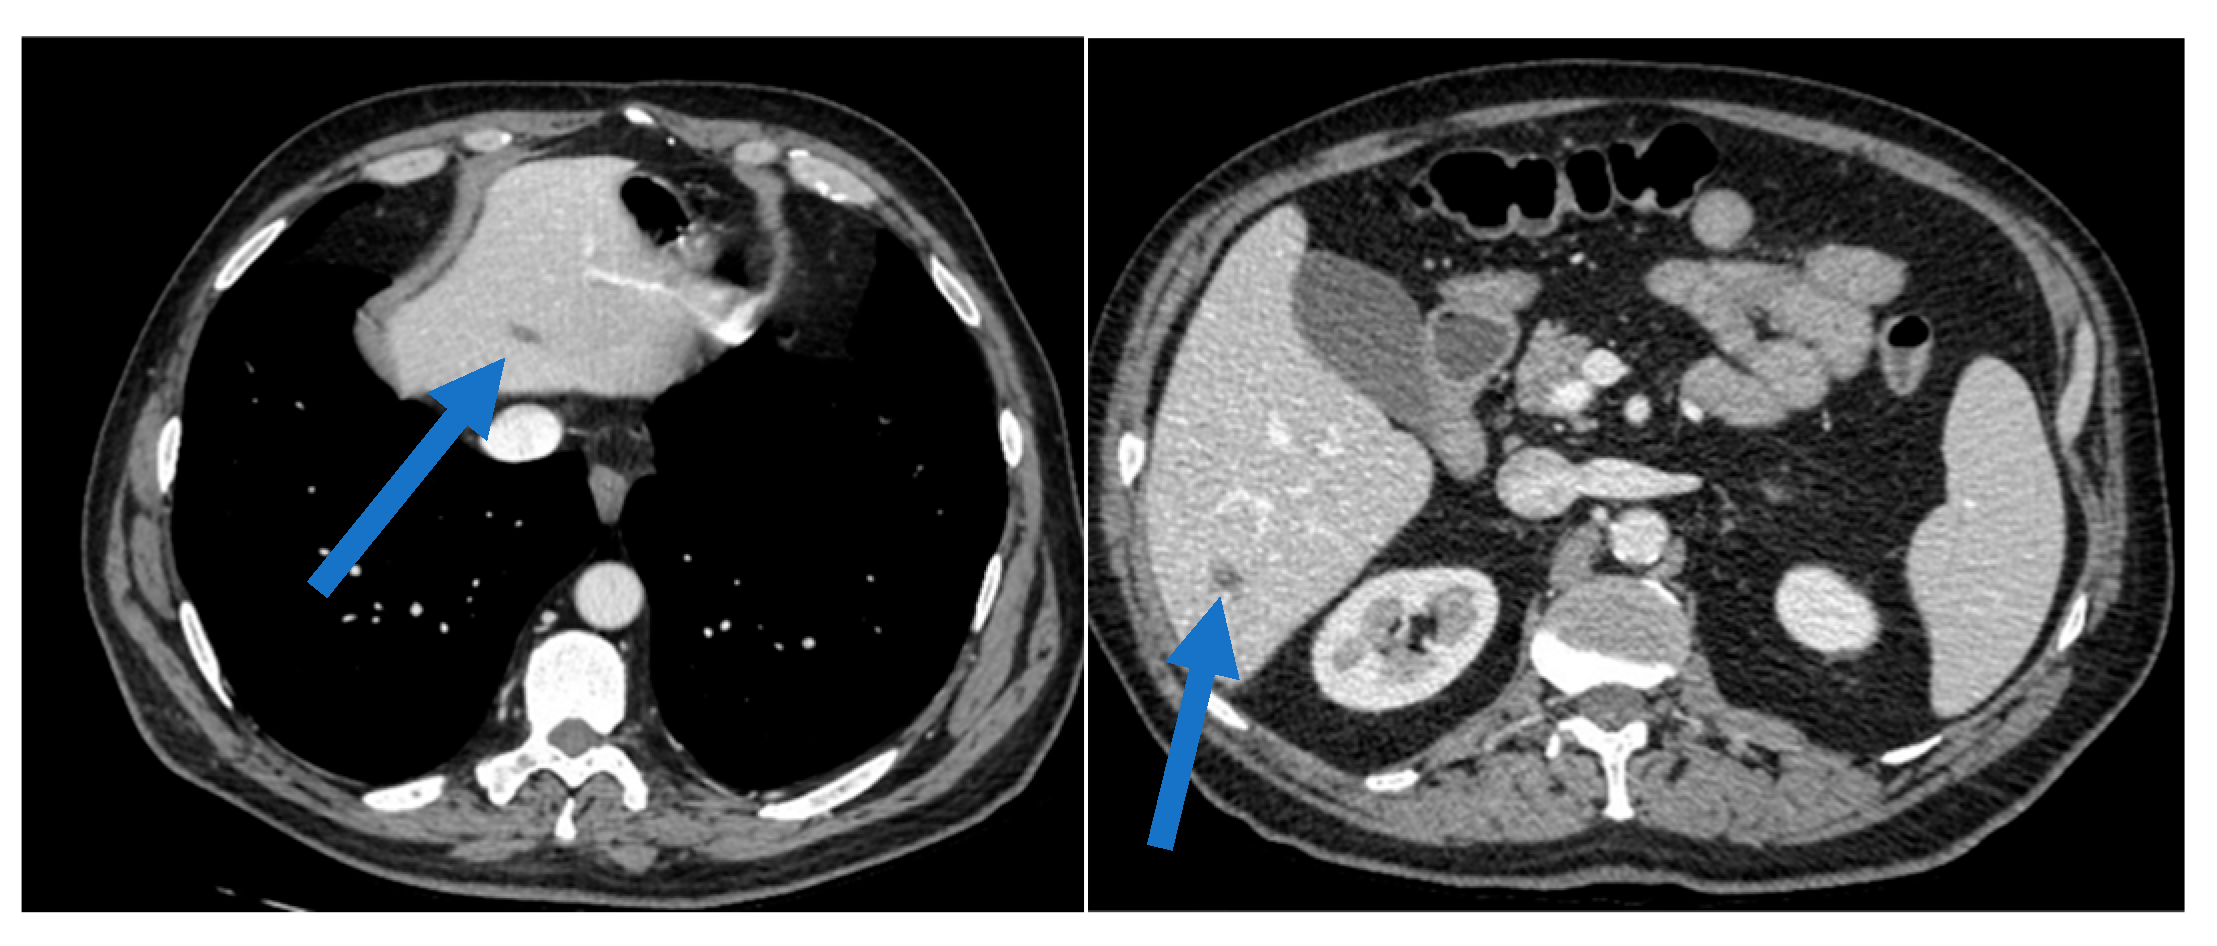

Clinical Course of Parotid Carcinoma with Hepatic and Nodal Metastases: A Case Report

2. Case Presentation